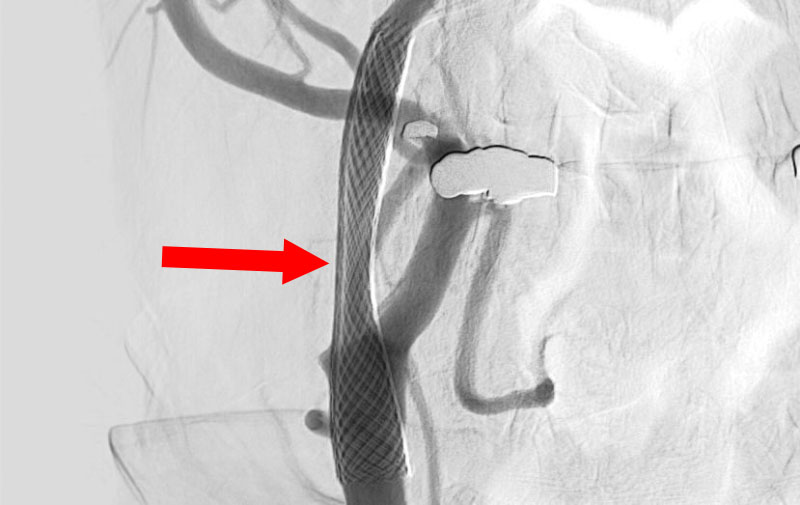

脳動静脈奇形

20代

愛知県の病院

No.1570 手術前

No.1570 手術中

No.1570 手術後